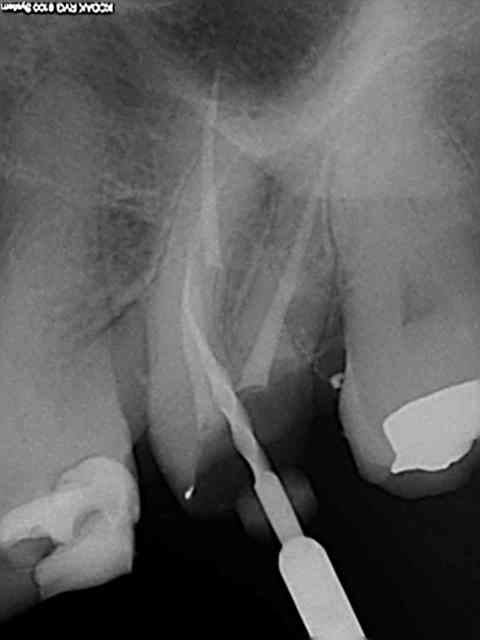

21/02/2014 à 01h05

Celui là m'a fait chier. je l'ai trouvé juste avant de prendre l'empreinte de mon ic-coiffe ( Têtu + plus de visibilité due à une cavité d'accès améliorée lol!) Spécial dédicace pour les pulpolithes qui ne m'ont pas facilité la tache.

L'orifice de ce petit enfoiré était juste à coté du canal palatin.